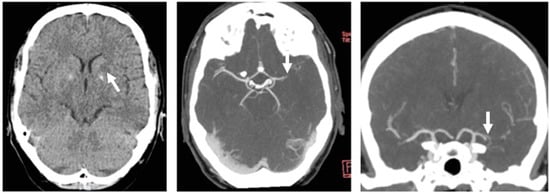

Case Report Continued